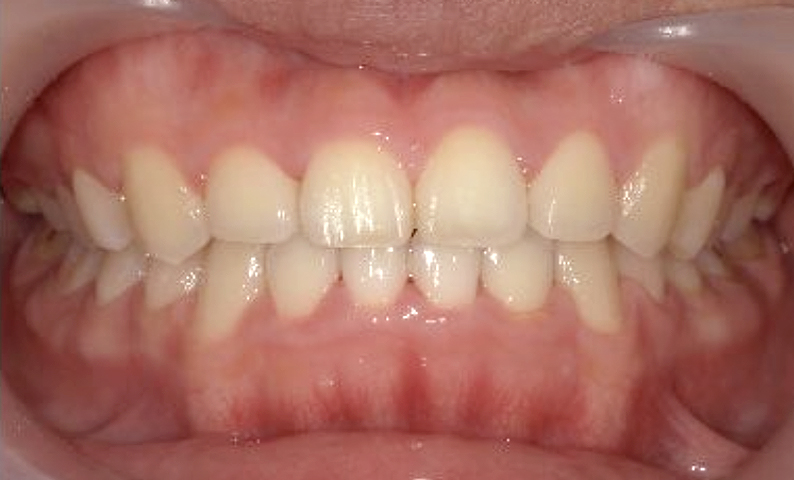

症例_022 上下顎の部分矯正

治療期間:7ヶ月金額:54万円+税女性前歯のガタガタ八重歯一部反対咬合

| Before | After |